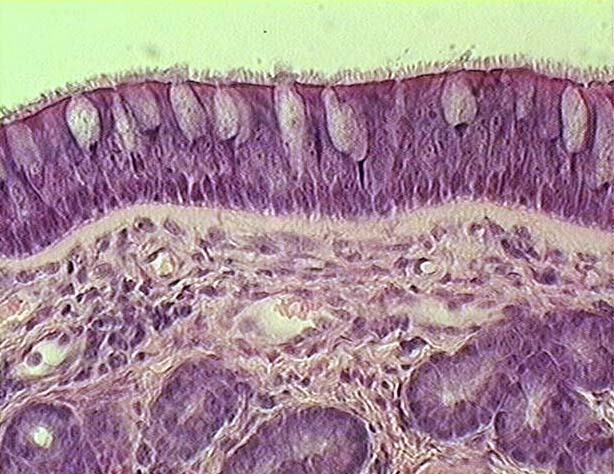

Respiratory Epithelium are made up of:

How would you classify respiratory epithelium?

pseudostratified columna

Describe the components seen on bronchi histology

Primary to tertiary bronchi

See respiratory epithelium: pseudostratidied columnar epithelium

underneath is Lamina Propria

under is smoot muslce with mast cells (issues d/t hitsamines)